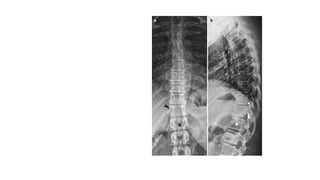

Thoracic spine

X-ray in AP and Lateral

projections.

Vertebral body (star ) of

T12 with rib hypoplasia;

T10–T11 intervertebral

foramina (circle ); T11

right pedicle(arrowhead )

Thoracic spine X-ray inAP and Lateral projections. Vertebral body (star ) of T12 with rib hypoplasia; T10–T11 intervertebral foramina (circle ); T11 right pedicle(arrowhead )